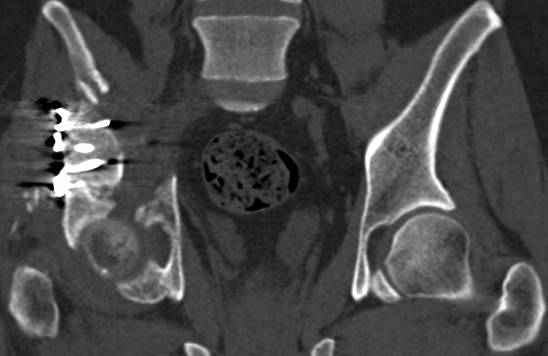

высылаю дополнительно сканы.

Судя по представленным реконструкциям (не очень хорошего качества - много наводок)

По отдельным срезам и тем более по реконструкции трудно судить о сращении крыла и задней колонны с осевым скелетом.

В большинстве случаев при двухколонных переломах

в итоге получается прочный бублик с дыркой. При эндопротезировании в дырку помещается головка, а чашка должна неплохо заклиниться в бублике.

Главное, чтобы бублик не был разорван, что не очень понятно на представленных снимках.

Поэтому хотелось бы дообследовать больного (разумеется включив стандартные проеции judet,и срезы показывающие сращение)

Все выступающие коллеги высказались насчет необходимости стандартных снимков по Judet, потому что для определения тактики лечения переломов вертлужной впадины 3Д снимки малоинформативны.

Из того минимума, что представлено, мне кажется, мы имеем дело с двухколонным переломом вертлужной впадины. Обычно медиальный (центральный) "вывих" головки встречаются в сложных двухколонных переломах со смещением.